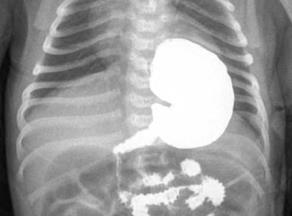

Рентгенологічне дослідження шлунку (мал. 2 В), кишківника (іригоскопія), нирок (екскреторна урографія мал. 2 Г), жовчного міхура (холецистографія мал. 2 Д).

мал. 9 нирки

Мал. 2 Г. Екскреторна урографія

6.3. Підготовка пацієнта до рентгенологічного дослідження нирок і сечовивідних шляхів (екскреторної урографії)

Основні етапи виконання:

1. За відсутності ознак йодизму безпосередньо перед обстеженням ввести пацієнту внутрішньовенно 20–60 мл контрастної речовини. Введення має бути дуже повільним. Під час введення медична сестра постійно спостерігає за станом пацієнта.

2. Після цього лікар проводить рентгенологічне дослідження нирок та сечовивідних шляхів.